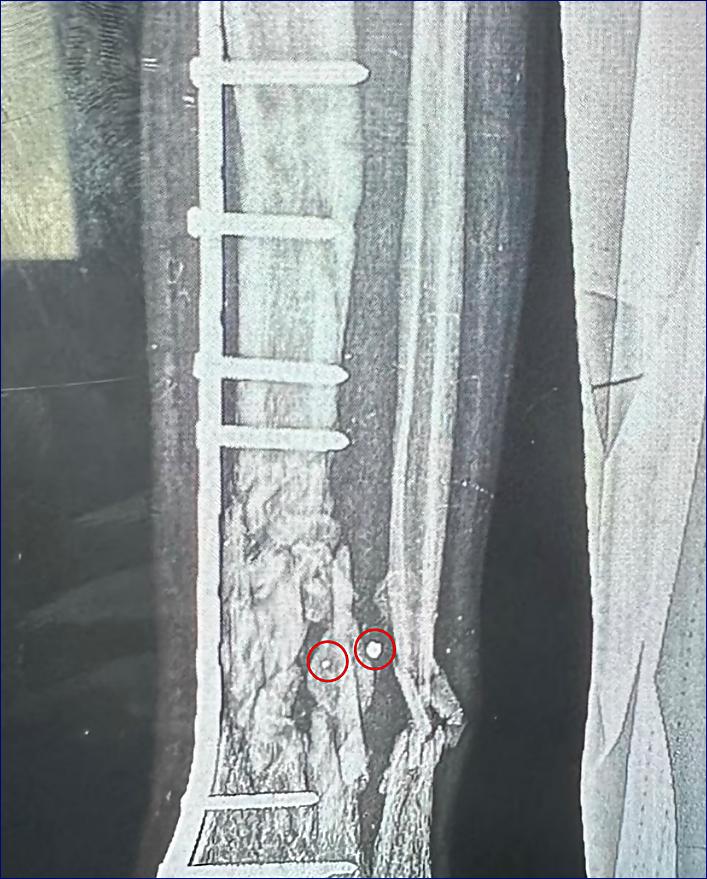

V úvodu tohoto článku je rentgenový snímek poškození nohy patnáctiletého chlapce střepinami, z nichž některé jsou stále zaseknuté v kosti. Chirurg řekl: "Střepina vnikla zleva do holenní kosti a vyšla přes lýtkovou kost vpravo od snímku. Náš výraz pro velmi roztříštěnou kost je "kominutovaná". Větší kominuce kostí se nevyskytuje." Chirurg vložil do holenní kosti destičku z nerezové oceli, která byla přišroubována.